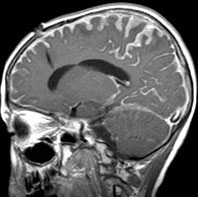

生下時に皮膚の大きな先天性色素細胞母斑があり脳MRIでみられたもの

有毛性母斑があるためにMRIが撮影されました。生後2ヶ月のものです。脳溝に沿うように,灰白質に浸潤するように,散在性の病変がみられます。脳幹部の前面から脳幹内部に浸潤するメラノーシスも特徴的です。